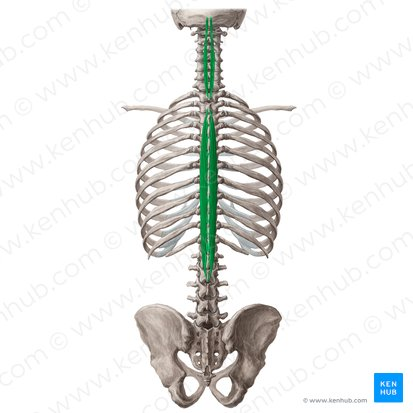

mm spinalis

Hållning